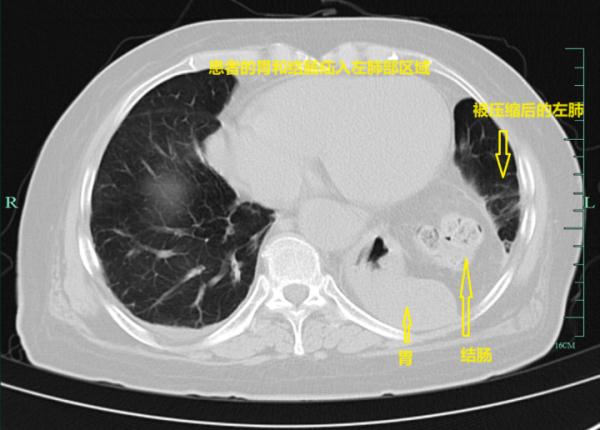

在疝和腹壁外科,黄永刚副主任经过CT检查,吴小姐简直不敢相信——她的胃和结肠竟齐刷刷“跑”到了肺里,左肺被挤成一点点。

最终,她被确诊患上了食道裂孔疝。

食管裂孔疝,通俗点理解,是指腹腔脏器通过扩大的食管裂孔进入胸腔所引起的疾病,通常是胃进入胸腔,也可能是结肠、网膜组织等腹腔脏器。

人的食管从胸腔下到腹腔间有一个通道,通道交界点就是食管裂孔,在某些因素作用下,食管裂孔被扩大,不仅能够通过食管,也能通过更大的器官,如胃,就形成了食管裂孔疝。

正常人进食后,食物应是一路向下走,但吴小姐吃下去的食物,在进入胃时需在胸腔滞留后再回到腹腔,这才导致了她进食后出现腹痛及反酸。